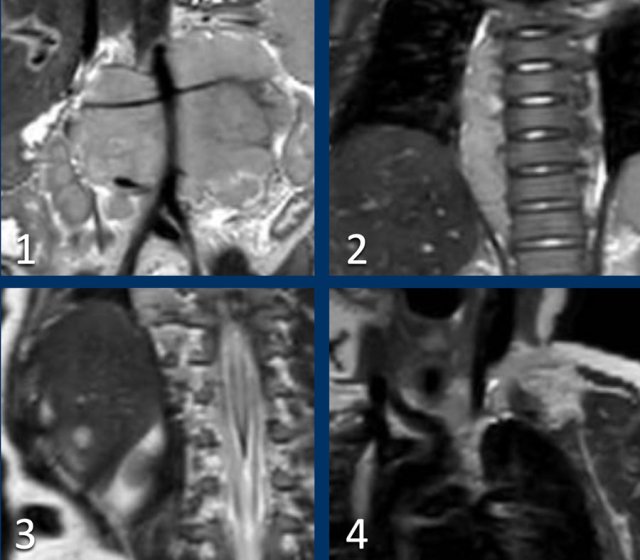

Scroll through the coronal T2 weighted series.

Study the images and then continue reading.

The findings are:

- Mass with encasement of the aorta and splanchnic vessels.

- Extension along the thoracic vertebral columns but no intraspinal invasion.

- Small liver metastases.

- Left supraclavicular mass.

Same patient.

This is an axial gadolinium enhanced T1W-image with fat suppression.

It shows the encasement of the vessels.

Notice the tumor extension posterior to the aorta, which is displaced away from the vertebral column (arrow).

The extent of the tumor is well appreciated on a 3D axial T2 weighted TSE series.

The left kidney is compressed and displaced caudally.

Para-aortal lymph node metastases are present (small yellow arrow).

The origins of the celiac trunc and superior mesenteric artery are encased by tumor (arrowhead).

The inferior caval vein is lifted anteriorly (green arrow).

Bilateral dorsal atelectasis is often seen on the MRI, because the examination is done under anesthesia.